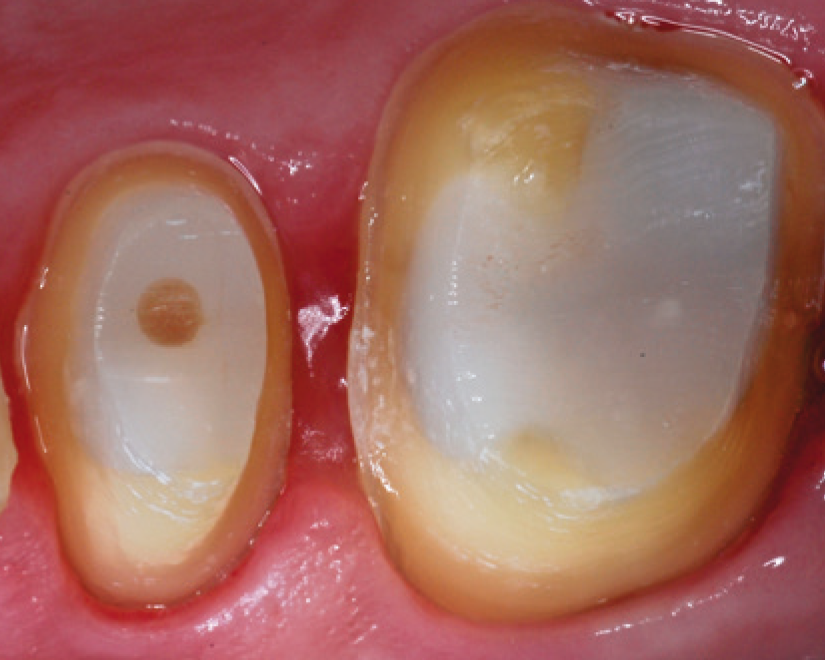

SDR® Plus is indicated for a variety of dental procedures, including the filling of Class I, II, III and V cavities, pit&fissure sealing, and even core build-ups before placing a crown. It is applied in its flowable state through injection from a syringe, or a small capsule called “Compula Tip”. After placement, SDR® Plus gets light cured by the application of blue light (440 – 480 nm wavelength) from a dental polymerization light. This allows the material to create a dense molecular network and replace the tooth substrate that was drilled away as a permanent restoration.

Start at the bottom of the box, slowly withdraw tip, wipe tip across cusp and allow to self-level for a few seconds. Do not use an instrument to manipulate as this can disturb the self-leveling behavior of the materials.